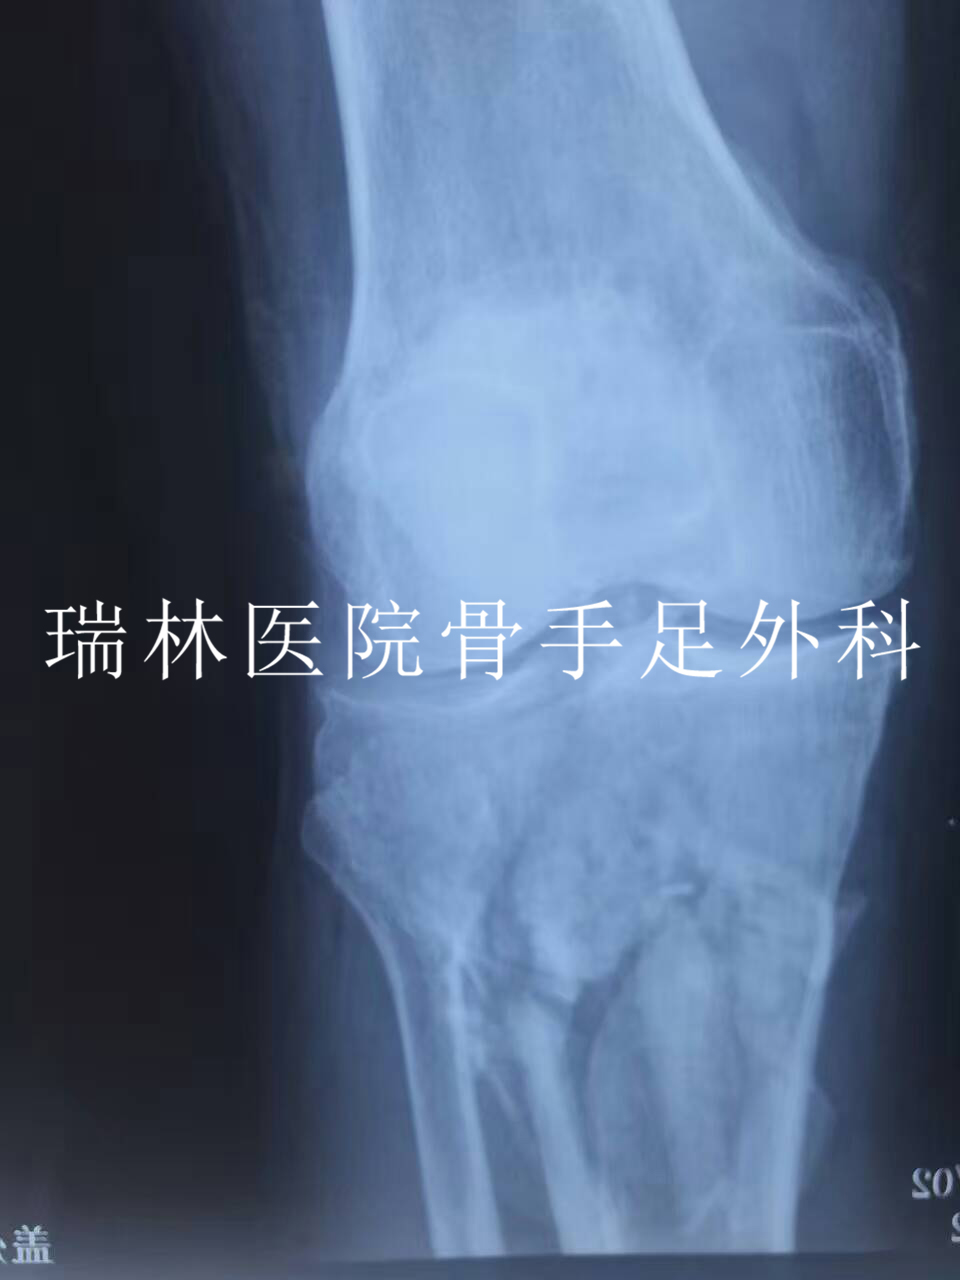

李XX断肢再植手术